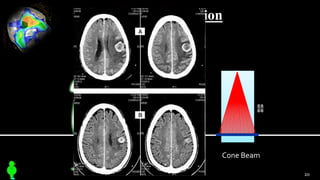

3 Cone Beam ComputedTomography

Cone Beam Formation

Cone Beam

20